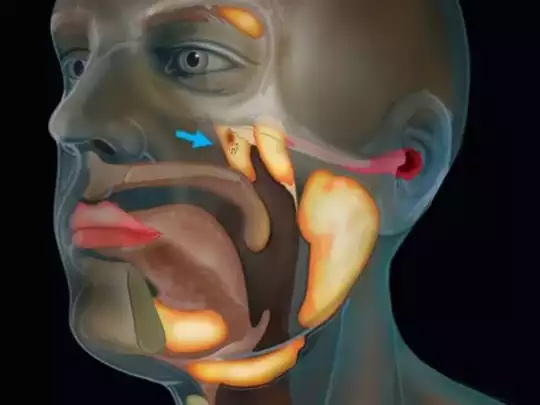

नीदरलैंड्स के वैज्ञानिकों ने इंसानों के गले में एक नया अंग खोज निकाला है। वैज्ञानिक एक नए 'कैंसर स्कैन' की जांच कर रहे थे जब उन्हें गले में एक नए अंग का पता चला। नीदरलैंड्स के कैंसर इंस्टिट्यूट के रिसर्चर्स को गले के ऊपरी हिस्से में दो लार ग्रंथियां (Salivary glands) मिले हैं जिन्हें ट्यूबेरियल सलाइवरी ग्लैंड (Tubarial salivary glands) नाम दिया गया है। ज्ञानिकों का मानना है कि यह अंग नाक के लूब्रिकेशन में मदद करता है।

नीदरलैंड के एम्सटर्डम के कैंसर इंस्टीट्यूट के वैज्ञानिक प्रोस्टेट कैंसर की जांच के लिए तैयार किए गए PSMA PET-CT नाम के स्कैन का परीक्षण कर रहे थे। इस दौरान डॉक्टर्स एक रेडियोएक्टिव ट्रेसर को मरीज के शरीर में इंजेक्ट करते हैं। रेडियोएक्टिव ट्रेसर की वजह से ही नए अंग का पता चला। स्टडी में दावा किया गया है कि ये ग्लैंड 1.5 इंच के हैं और ये टोरस ट्यूबेरियस (Torus Tubarius) नाम के कार्टिलेज के एक हिस्से के ऊपर हैं। रिसर्चर्स का कहना है कि शायद इनका काम नाक और मुंह के पीछे गले के ऊपरी हिस्से को ल्यूब्रिकेट करना होगा।

रेडियोथेरपी ऐंड ऑन्कॉलजी जर्नल में छपी स्टडी में रिसर्चर्स ने पुष्टि की है कि करीब 100 मरीजों पर स्टडी में ये ग्लैंड पाए गए हैं। माना जा रहा है कि इस खोज से कैंसर के इलाज में मदद मिल सकती है। अभी तक माना जाता था कि नाक के पीछे के इस हिस्से (Nasopharynx) में कुछ नहीं होता है। वहीं, तीन सलाइवरी ग्लैंड भी जीभ के नीचे, जबड़े के नीचे और जबड़े के पीछे होते हैं, यही माना जाता था।